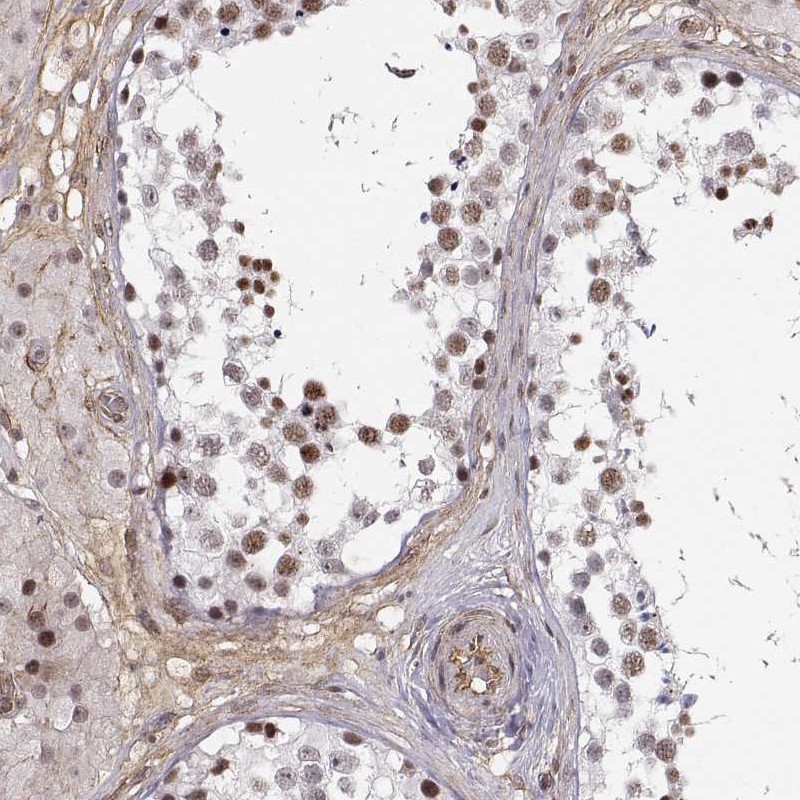

Immunohistochemical staining of human testis shows moderate nuclear positivity in cells in seminiferous ducts and Leydig cells.